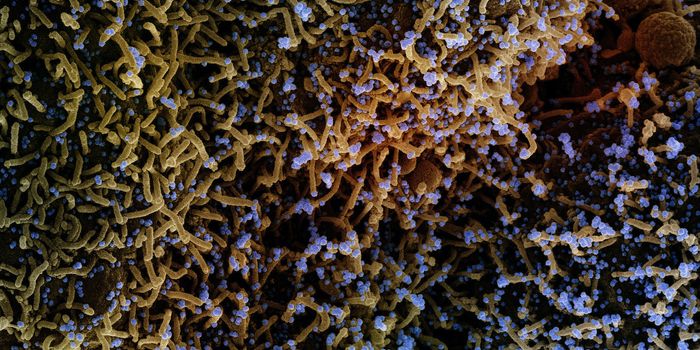

FEB 21, 2020Clinical & Molecular DXDiagnosing coronavirus is done through next-generation sequencing, real-time RT-PCR tests, cell culture, and electron mi ...